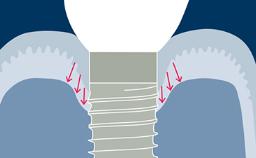

种植治疗已被证明是一种成功的治疗方式,它适用于广泛的牙齿修复临床适应症。虽然如此,但还是会出现并发症,有确凿的证据表明牙种植体的修复并发症发生率比天然牙齿高。这些并发症通常被称为“硬件并发症”,务必要了解它们的起因和最佳处理方式。本模块将对固定修复体的种植硬件并发症进行分类,然后根据分类阐明其不同的起因、最佳预防方法和处理方法。